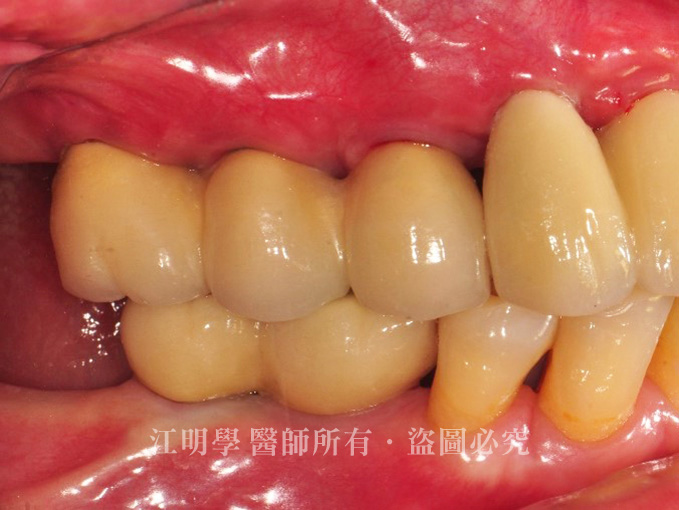

來看看李太太在接受植牙治療前後的對比:

經過數個階段性治療,李太太的牙齒補齊了,非常滿意治療的成果。

治療後:咀嚼功能明顯提升

治療後:缺牙問題解決,笑起來更有自信